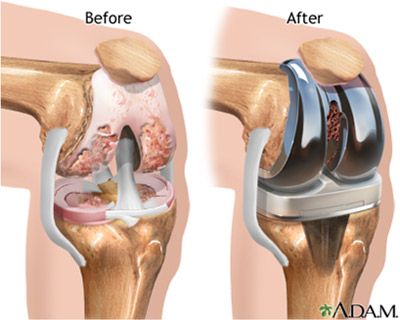

The surgery is performed under general anesthesia. Your surgeon will make a small incision in the front area of your diseased knee so that he can access the kneecap (patella). He then rotates the kneecap outwards to be able to see the internal area where the surgery needs to be done.

The surgeon then uses special equipment to precisely cut bone and cartilage from the damaged portion of the femur (thighbone) and resurfaces it. This is followed by placing a metallic implant with the help of bone cement that seals it and recreates the surface of the joint.

Now the shinbone (tibia) is resurfaced in a similar way and a medical-grade plastic tibial component is placed to provide a smooth gliding surface. The bottom portion of the plastic implant is called tibial tray and is set with the bone using bone cement.

Lastly the patella is set at its original place. But before the surgeon fits it in, he uses another plastic component to make sure it sets properly with the rest of the implant.

Once all this is complete, the surgeon would examine your knee by bending it so that the alignment, size and positioning of the implant can be checked. If all is perfectly fine then the incision area is closed either with stitches or staples.